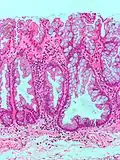

| Гиперпластический полип | Зазубренные неветвистые крипты | Нет | ![]() |

Синдром гиперпластического полипоза (множественные полипы) |